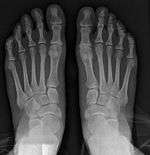

It is leaning of the first metatarsal bone away from the second metatarsal and towards the opposite foot (Fig. 1). As it leans over, its head sticks out to form the bunion bump and it also widens the forefoot to cause shoes feeling too tight. Thus when bunion pain becomes unmanageable, surgical correction is to narrow the forefoot by repositioning of the first metatarsal head back to its normal position. This can be done by osteotomy (bone-breaking), soft tissue (non-osteotomy) or fusion techniques.